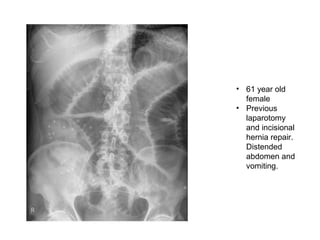

• 61 year old

female

• Previous

laparotomy

and incisional

hernia repair.

Distended

abdomen and

vomiting.

• 61 yearold female • Previous laparotomy and incisional hernia repair. Distended abdomen and vomiting.

Small Bowel Obstruction •epidemiology 1 • 80% of all mechanical bowel obstruction • average age: 64 years • females comprise 60% of patients • presentation • abdominal distension, nausea and vomiting • the level will determine the acuity of presentation • high obstruction presents early, possibly with bilious vomiting • lower obstruction presents late and may have faeculent vomiting • pathology • may be complete or incomplete • causes • adhesional SBO: occurs almost exclusively from prior surgery • herniae (often femoral or inguinal, but incisional occur) • foreign bodies or other masses, e.g. gallstones • rare: small bowel tumours causing intussusception